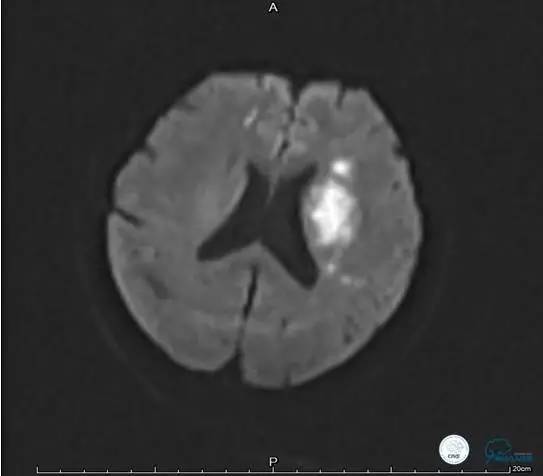

患者:49岁男性,左侧偏瘫1个月,药物治疗、康复训练效果不好,转我院,肌力0~1级。

core-clilnical明显不匹配,是介入开通的合适患者。